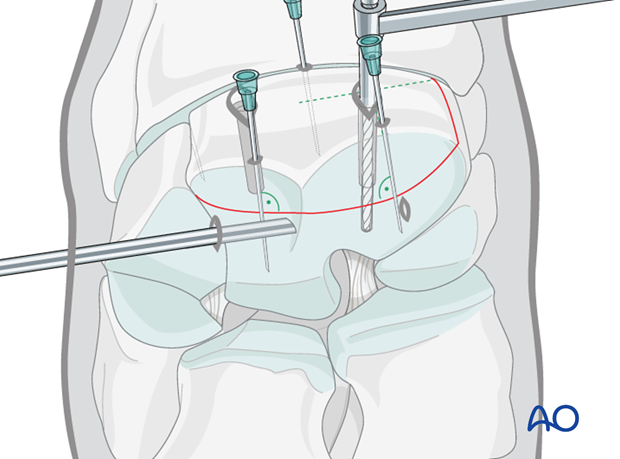

The 3.2 mm drill guide is inserted into one glide hole and the 3.2 mm thread hole is drilled through the remaining third carpal bone. The hole is drilled through the entire parent third carpal bone so that maximal screw length can be used.

The first hole is countersunk at the dorsal surface and debris is flushed.

Correct screw lengths are determined using a depth gauge. The screws used are generally 36 mm long.

The first hole is tapped with a 4.5 mm tap protected by the corresponding drill guide. This should be done by hand.

The first 4.5 mm cortex screw of appropriate length is inserted and tightened under arthroscopic visualization.

Preparation of the thread hole, countersinking, determining the depth of the hole and tapping of the thread hole are subsequently performed, followed by inserting and tightening of the second screw. After the screws are tightened remove any debris or elevated cartilage at the fracture line.

Pearl: Use two fingers and thumb when doing final tightening, thereby avoiding excessive torque and potential breaking of screw head. Intraoperative radiographs are taken to confirm screw length and correct positioning.